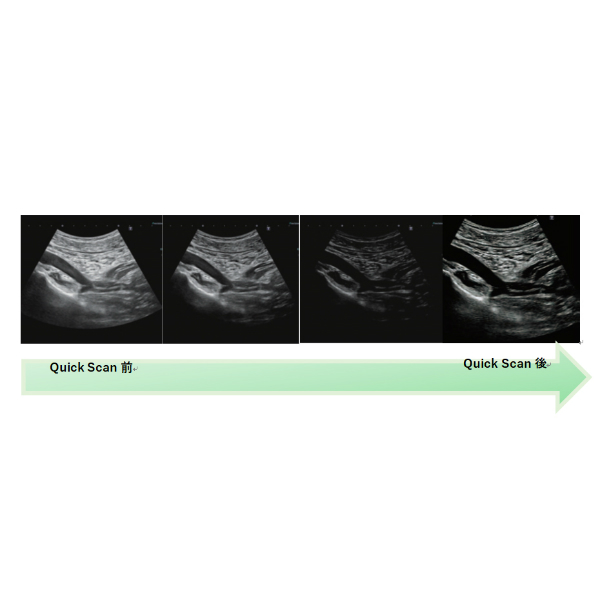

●i-seriesのテクノロジーを受け継いだ、送受信信号処理が、均一かつ高精細画像を提供